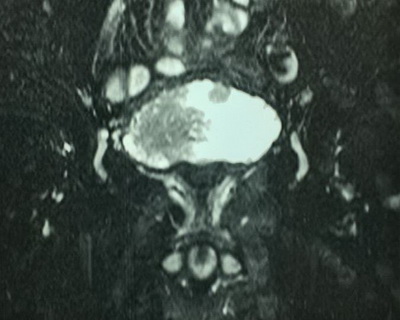

Диагноз: Рак мочевого пузыря T2bNoMo. Кисты правой почки.

Очередной эпизод макрогематурии отметил в начале декабря текущего года. Консультирован в клинике урологии УКБ№2 Первого МГМУ им. И.М.Сеченова, при обследовании (УЗИ, МРТ и МСКТ) диагностировано до 20 объемных образований мочевого пузыря. Госпитализирован в плановом порядке для обследования и лечения.